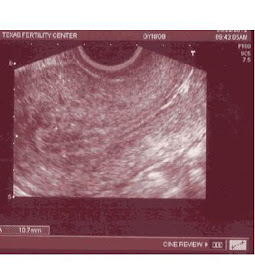

At 9:30, I drove to Texas Fertility for my lining check.  Dr. Hansard did the ultrasound.  I really like her!  This was our second appointment together and she's just no-nonsense and to the point.  She agreed that it's silly to be driving to Houston for lining checks, but what can you do?  She also thinks that the check I had on Friday was inaccurate.  13.1 would be too far along for 2 weeks prior to transfer (her eyes about bugged out of her head when I said 13.1-- she was thinking our cycle was doomed).  She measured my lining at 10.7mm, which she said was much better.

The visual:

How exciting, right?  Triple stripe pattern and all that jazz.